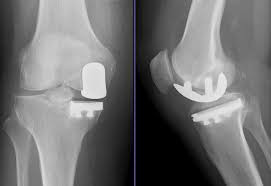

Однокомпартментное эндопротезирование коленного сустава (UKA) является хирургической альтернативой тотальному эндопротезированию коленного сустава (TKA) для лечения однокомпонентного остеоартрита.Однако данные о частоте неудач УКА показывают 7-летнюю выживаемость 74%, что значительно ниже, чем у ТКА (92%).Хотя собственные факторы пациентов увеличивают риск неудачи, например, более молодые пациенты и более высокий индекс массы тела (ИМТ), могут увеличить риск неудачи УАК, хирургические технические ошибки считаются важными факторами риска ранней неудачи.В UKA сложно добиться оптимального выравнивания протеза и выступа (выступа).Размер большеберцового протеза должен быть установлен и имплантирован таким образом, чтобы свести к минимуму раздражение мягких тканей, и было показано, что медиальный выступ большеберцовой кости более 3 мм является значительным фактором риска снижения шкалы Oxford Knee Score (OKS) и усиления боли.Основная цель этого исследования состояла в том, чтобы оценить общие клинические и визуализационные результаты UKA.Вторичной целью было оценить влияние неправильного прилегания и выступания протеза на приживаемость имплантата. Однокомпартментная артропластика коленного сустава (UKA) является хирургической альтернативой тотальной артропластике коленного сустава (TKA) для лечения одномаскулярного остеоартрита.Однако данные о частоте неудач УКА показывают 7-летнюю выживаемость 74%, что значительно ниже, чем у ТКА (92%).Хотя собственные факторы пациентов увеличивают риск неудачи, например, более молодые пациенты и более высокий индекс массы тела (ИМТ), могут увеличить риск неудачи УАК, хирургические технические ошибки считаются важными факторами риска ранней неудачи.В UKA сложно добиться оптимального выравнивания протеза и выступа (выступа).Размер большеберцового протеза должен быть установлен и имплантирован таким образом, чтобы свести к минимуму раздражение мягких тканей, и было показано, что медиальный выступ большеберцовой кости более 3 мм является значительным фактором риска снижения шкалы Oxford Knee Score (OKS) и усиления боли.Основная цель этого исследования состояла в том, чтобы оценить общие клинические и визуализационные результаты UKA.Вторичной целью было оценить влияние неправильного прилегания и выступания протеза на приживаемость имплантата.

Это исследование было одноцентровым, в него вошли пациенты мужского и женского пола, которым в нашем учреждении была выполнена медиальная УКК с января 2008 г. по декабрь 2017 г., и всем пациентам выполнялась УКК с использованием стандартных методов. артрит, смещение большеберцовой кости сзади и нестабильность.Клинические и визуализационные результаты были получены из ретроспективного обзора клинических записей и институциональных баз данных.Бедренный корональный и сагиттальный углы (FCA и FSA) и большеберцовый корональный и сагиттальный углы (TCA и TSA) были измерены на рентгенограммах для всех UKA с фиксированной и подвижной платформами, как показано.

Только 11,9% UKA достигли желаемого выравнивания и ортопедического покрытия.Передний выступ протеза не был значимым фактором риска отказа ОАК (частота отказов 10,0%, р=0,090), а задний выступ протеза (25,0%, р=0,006) и медиальный выступ протеза (38,2%, р=0,090). <0,001) были значимыми факторами риска неэффективности UKA.

В этом исследовании мы оценили клинические и визуализационные результаты медиального UKA, а также влияние выравнивания и выступания протеза.5- и 10-летняя выживаемость составила 88 и 70% соответственно и была значительно ниже, чем при ТЭК.наиболее частыми показаниями к ревизии были плохое выравнивание протеза, механическая поломка и прогрессирование остеоартрита.Плохое выравнивание протеза и задний и медиальный выступы являются важными факторами риска для ревизии UKA.